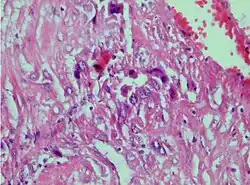

Photomicrograph showing proliferating intermediate trophoblast with scarce cytotophoblastic and syncytiotrophoblastic elements | |